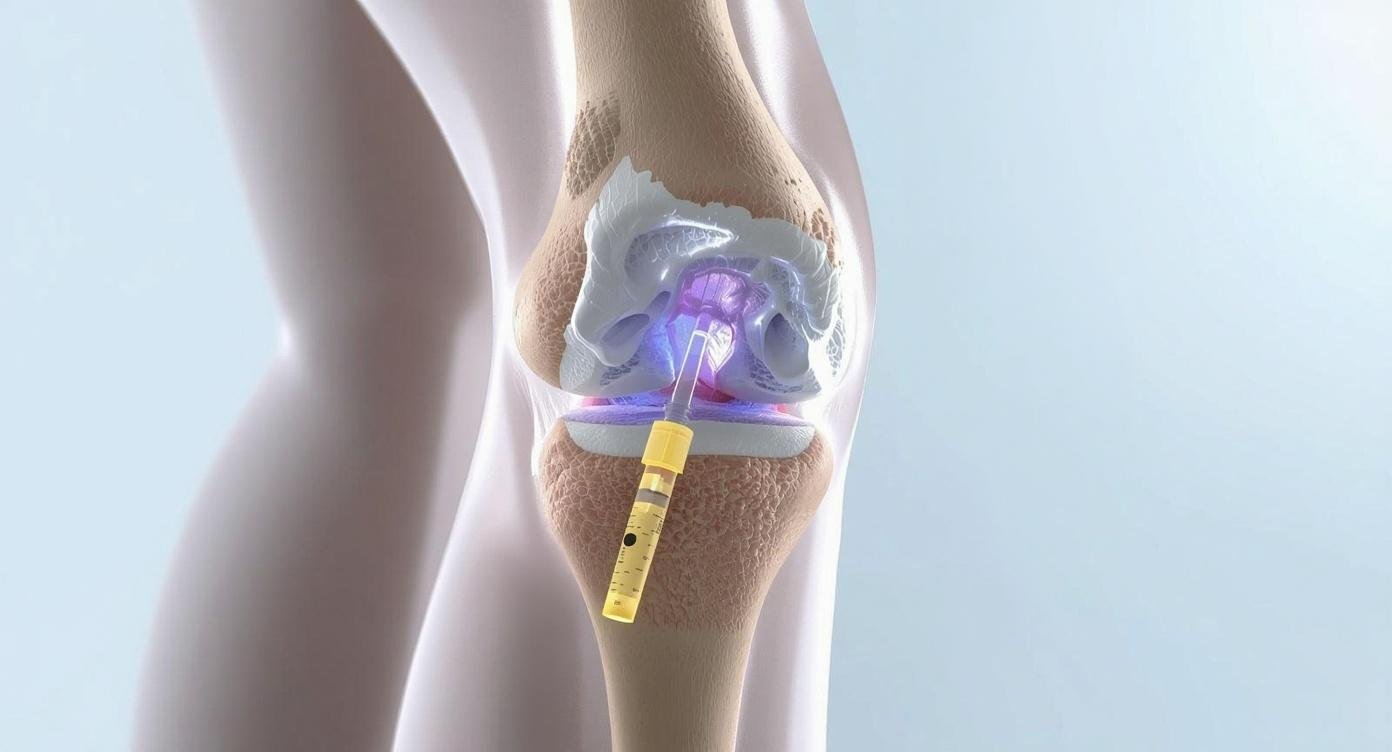

في AneMara Joint Clinic نقدم حقن الهيالورونيك للركبة تحت إشراف أفضل الأطباء المتخصصين، بهدف تخفيف آلام المفاصل وتحسين الحركة بشكل آمن وفعال. تُعتبر هذه الحقن خيارًا علاجيًا متقدمًا للمرضى الذين يعانون من خشونة الركبة أو الفصال العظمي، خاصة عند فشل الأدوية التقليدية في السيطرة على الألم.

حمض الهيالورونيك مادة طبيعية موجودة في الجسم، خاصة في المفاصل، تساعد على تليين الحركة وتقليل الاحتكاك. عند نقص هذا الحمض بسبب التقدم في العمر أو الإصابة بالخشونة، تقل جودة السائل الزلالي في الركبة مما يزيد الألم وصعوبة الحركة.

في AneMara Joint Clinic، تُجرى الحقن بطريقة آمنة وفعالة لتعويض نقص حمض الهيالورونيك وحماية الغضروف، وتحسين الحركة اليومية للمريض.

طريقة الحقن وعدد الجلسات

- يتم الحقن مرة في الأسبوع لمدة 3 إلى 5 أسابيع حسب نوع الحقن واستجابة الجسم.

- تستغرق العملية حوالي 10-20 دقيقة لكل جلسة.

- النتائج الأولية تظهر خلال أيام قليلة إلى أسبوع، بينما التأثير الكامل يمكن أن يستمر من 6 أشهر إلى سنة حسب حالة المريض.